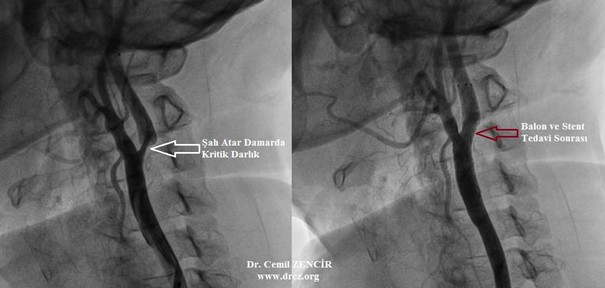

Özellikle mitral darlığı olan uygun hastalarda uygulanan ameliyat dışı bir tedavi seçeneğidir. Hastanın kasık bölgesi lokal anesteziyle uyuşturulduktan sonra atardamara bir kateter yerleştirilir. Bu kateter dar olan mitral kapağa ilerletildikten sonra ucundaki sosis benzeri balon şişirilerek darlık açılır. Daha nadiren diğer kapakların darlıklarında da bu yöntem tercih edilebilmektedir.